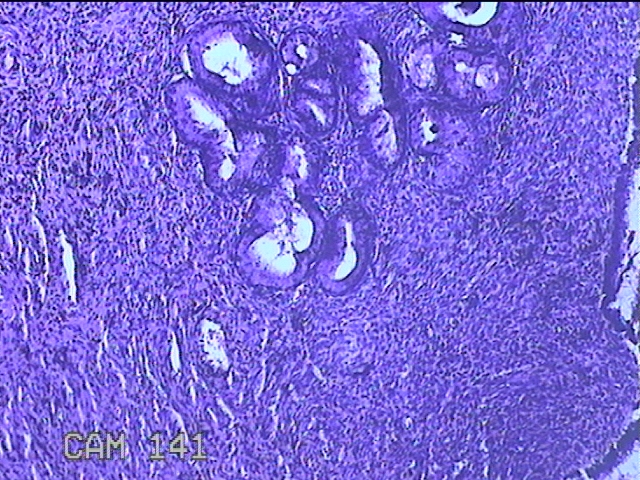

宫颈赘生物

性别

女

年龄

49岁

临床诊断

人乳头瘤病毒感染

一般病史

宫颈HPV阳性TCTLSLL

标本名称

大体所见

灰白粉红色肿物1.2x0.8x0.2cm两个,表面光滑。

图1